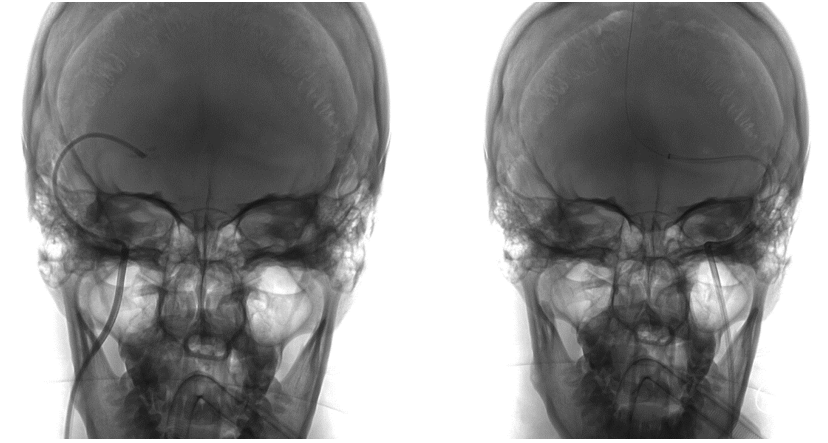

撤除微导管,选用Precise 8*40mm支架,沿Floppy 300微导丝尝试将Precise支架越过狭窄段失败。撤出支架,沿Floppy 300微导丝将Tethys®中间导引导管顺利送达左侧横窦远心端。再利用特洛伊木马技术将Precise支架推送到位,回撤Tethys®中间导引导管,支架定位准确后成功于跨左侧横窦-乙状窦狭窄处释放。

在Tethys®中间导引导管下支架顺利通过左侧横窦乙状窦交界处

再次将XT-27微导管穿过支架送至横窦远心端,对支架远近端进行测压,支架远端压力22mmHg,近端21mmHg,压力差为1mmHg。复查造影提示左侧横窦狭窄显著改善,DynaCT未见颅内出血。遂结束手术。